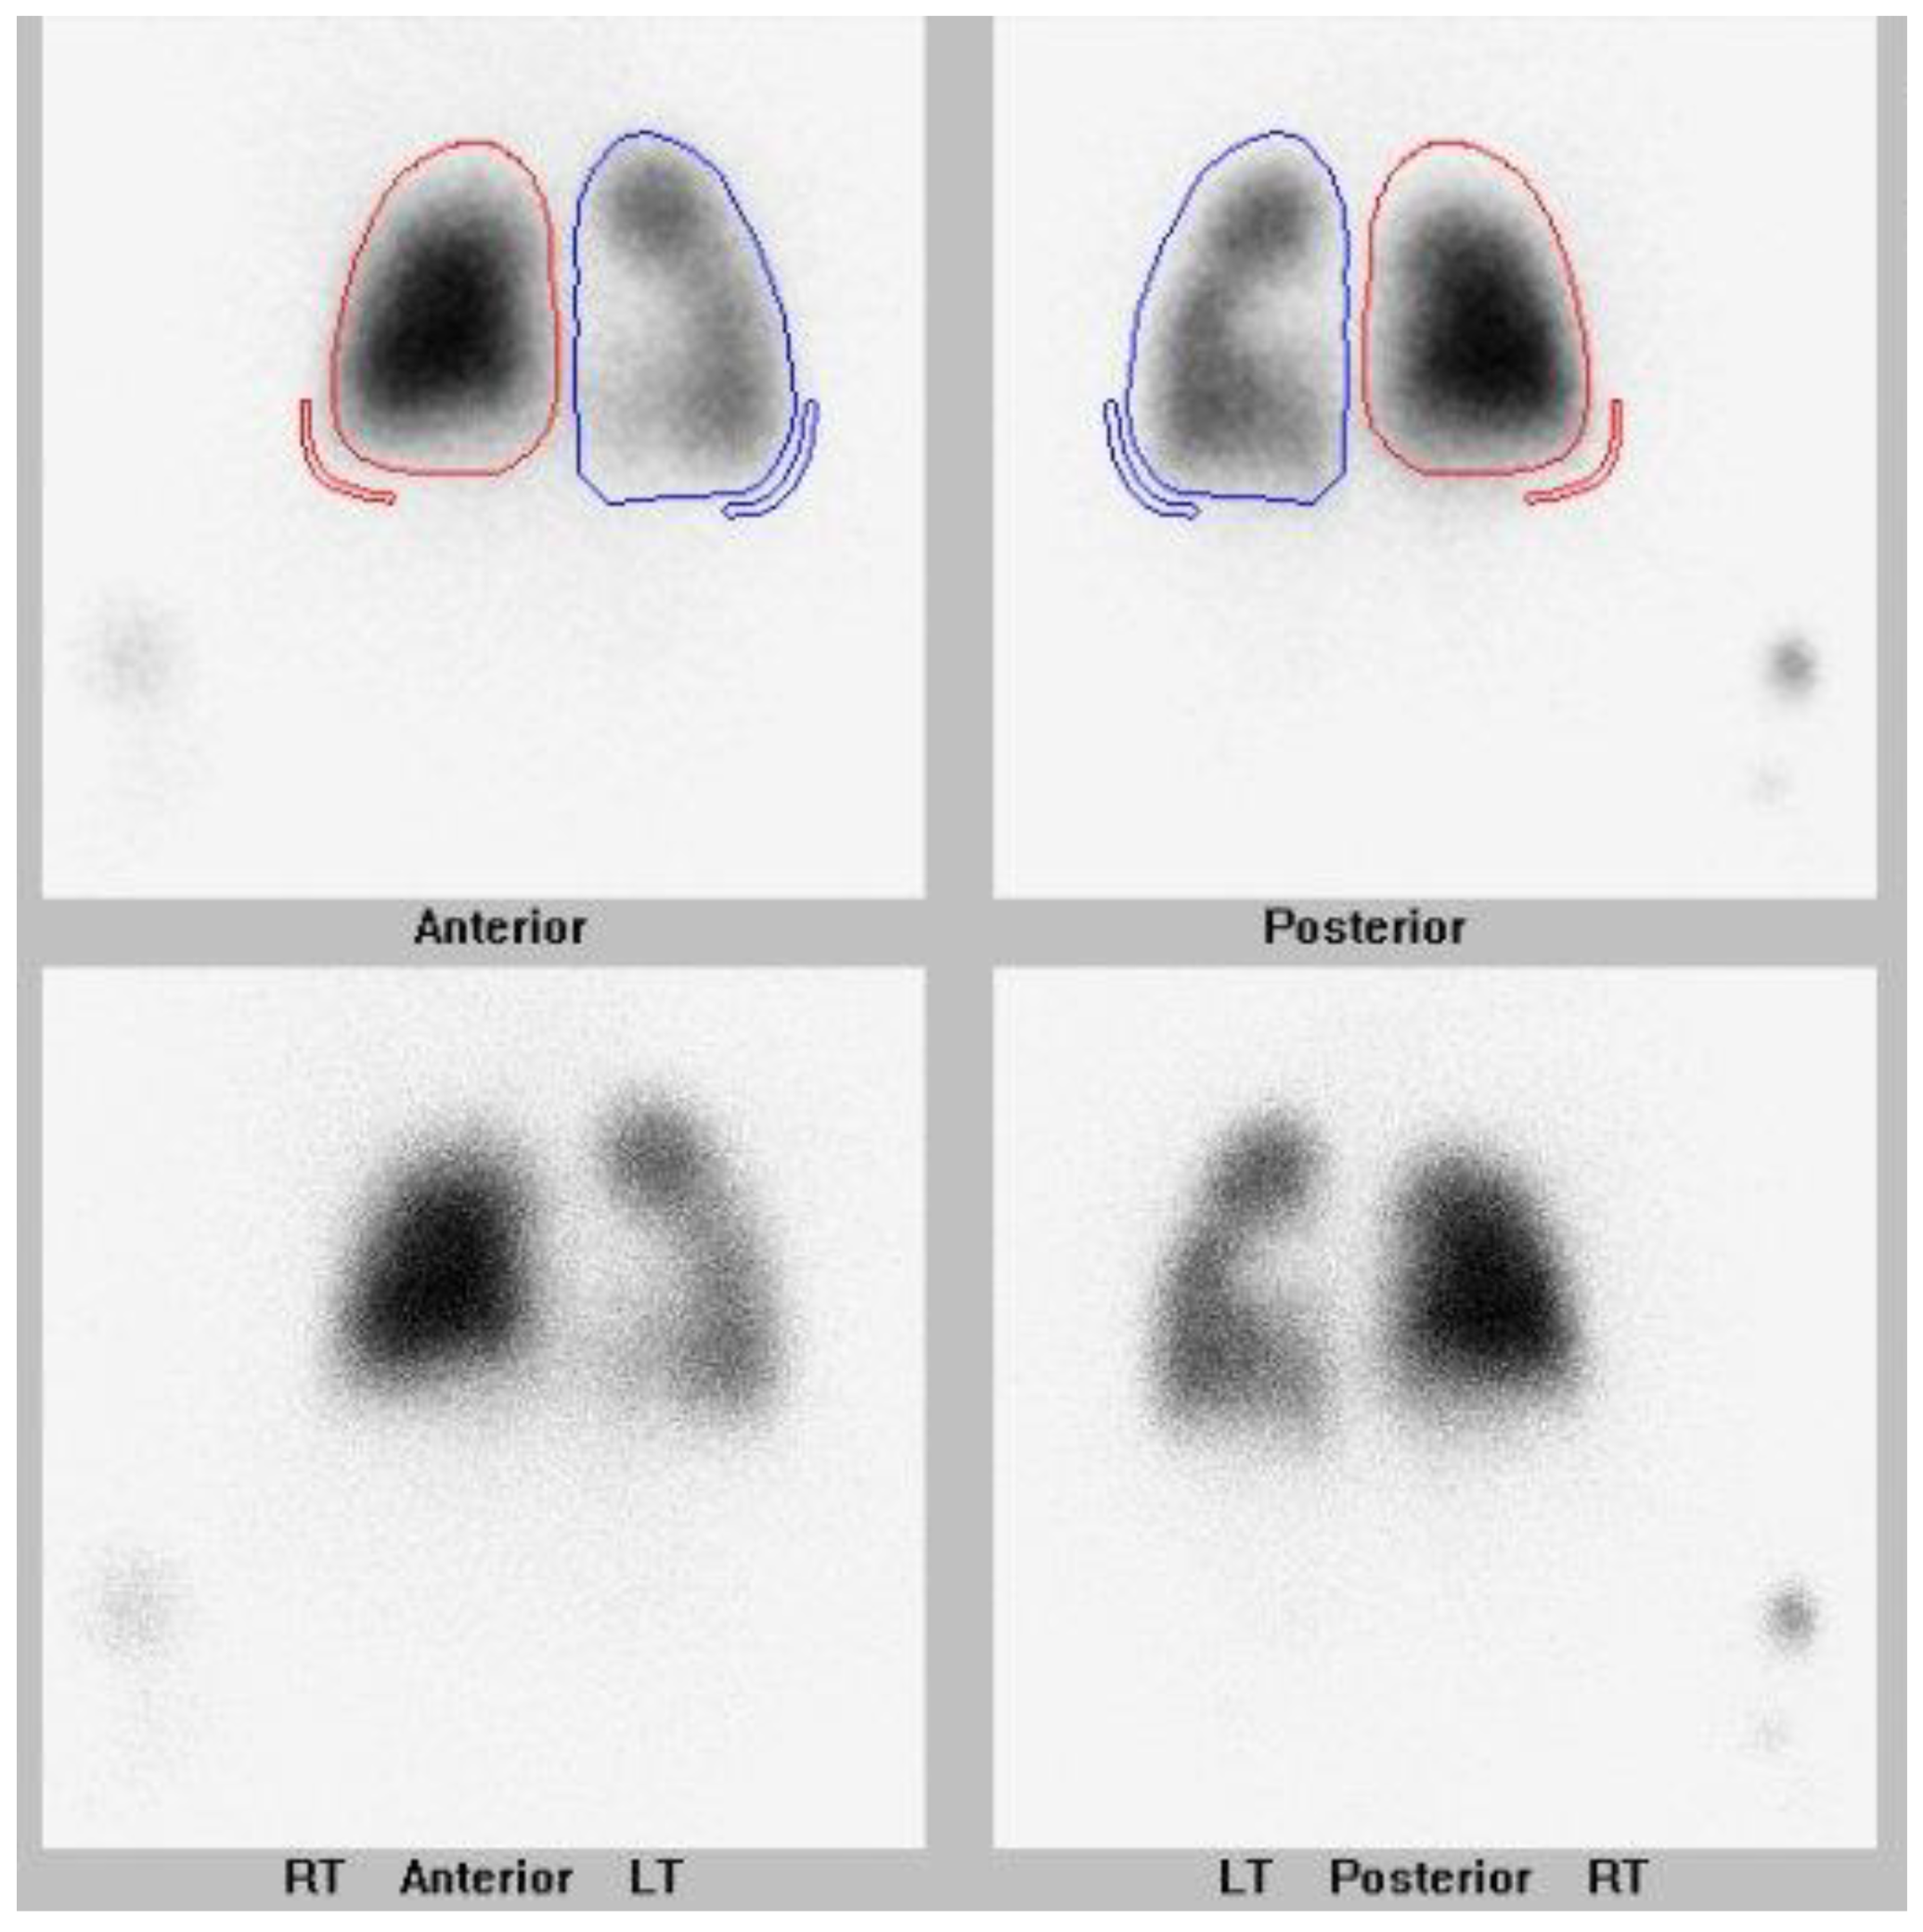

They also had a history of bronchopulmonary dysplasia and anemia of prematurity. They were presented at their local hospital surgical conference at age 5 months upon the newly diagnosed PVS. The hospital deemed them not to be a surgical candidate, and the family sought a second opinion. The lung scan performed pre-catheterization is shown in Figure 1.

Figure 1. Nuclear lung perfusion scan of a 6 month old patient with a history of bilateral upper pulmonary vein stenosis. Image is pre-intervention. Differential pulmonary perfusion as quantitated based on Tc-99m MAA localization is 56% left and 44% right lung. There is decreased perfusion to the right upper lung. Right lung is outlined in red. Left lung is outlined in blue.